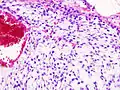

Патологическая анатомия

Хондросаркома — злокачественная опухоль хрящевого строения. Хондросаркома периферической локализации хорошо выявляется в виде плотной опухоли, прилегающей к кортикальному слою кости, иногда прорастающей в кость на различную глубину. В ней могут быть очаги оссификации и петрификаты. Опухоль плотноэластической консистенции, при наличии ослизнения, распада или кровоизлияний — более мягкая, не имеет ясного ограничения от соседней ткани. При разрезе нетрудно определить хрящевой её характер. При микроскопическом исследовании опухоль напоминает иногда хондрому, состоит из незрелых клеток с резко выраженным клеточным атипизмом. Часто рисунок опухоли имеет вид микросаркомы, в которой можно найти участки хрящевой ткани с плохо оформленными ячейками, содержащие неправильной формы хондробласты.